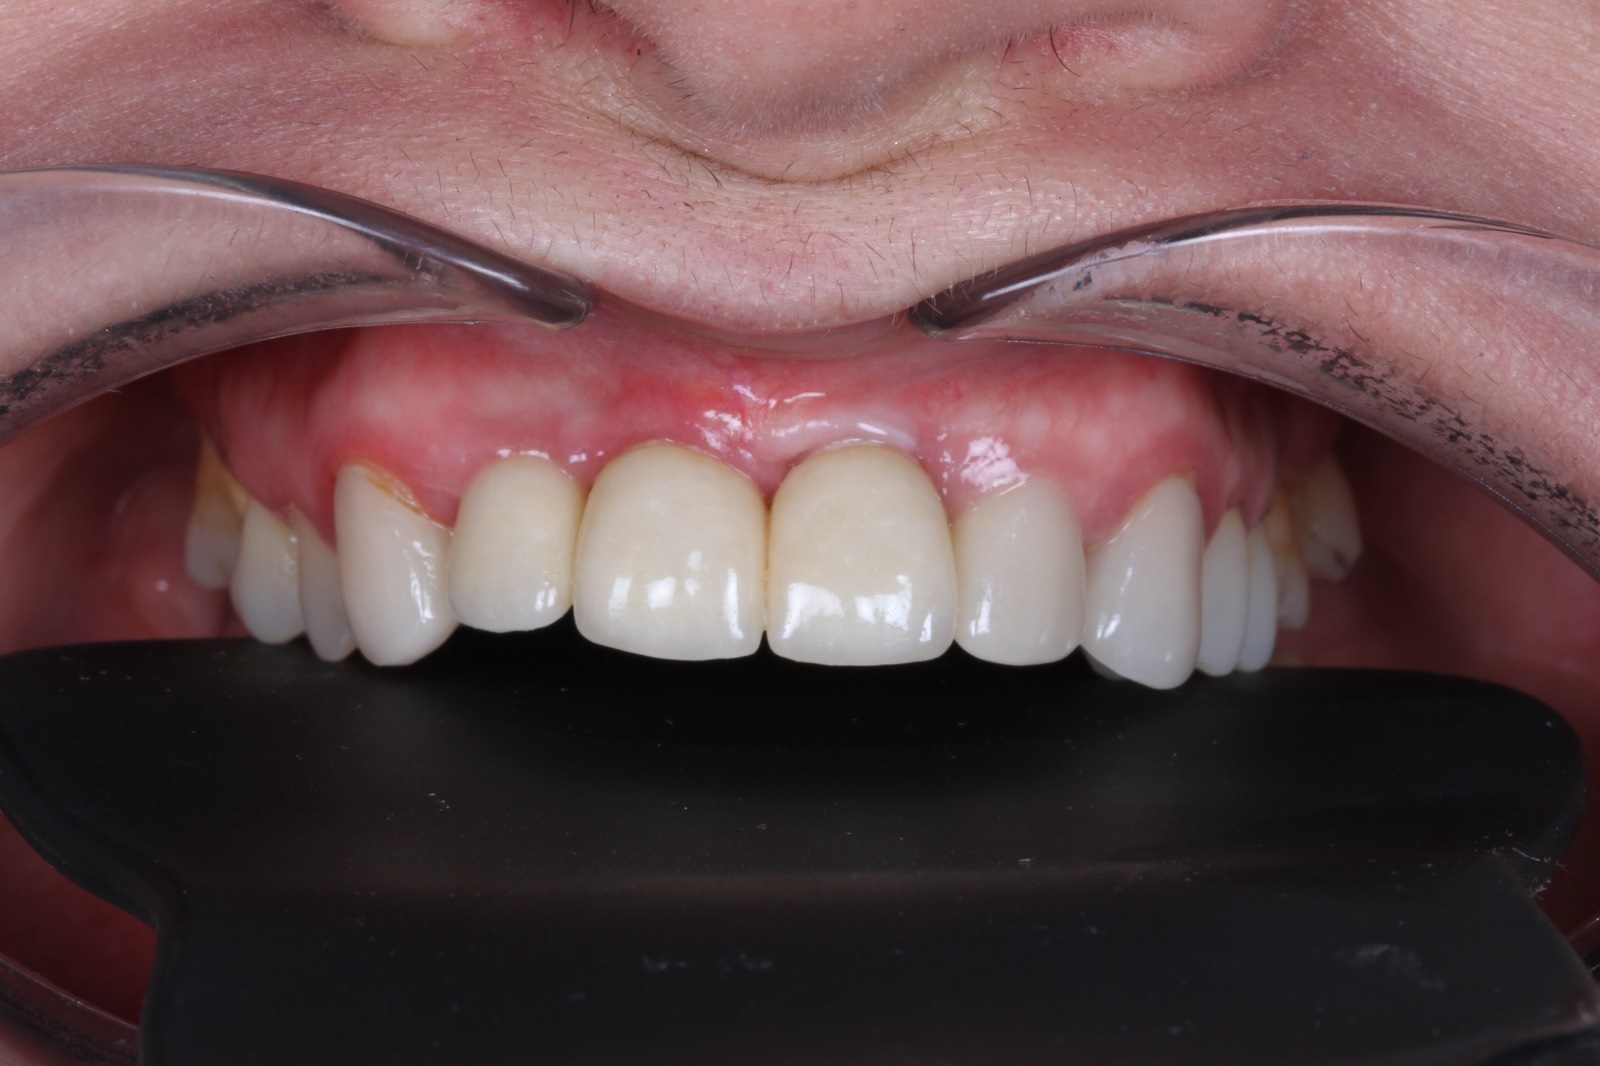

Установлено 4 имплантанта Osstem во фронтальном участке верхней челюсти.

Протезирование выполнено коронками из оксида циркония с фиксацией на абатменты из оксида циркония.